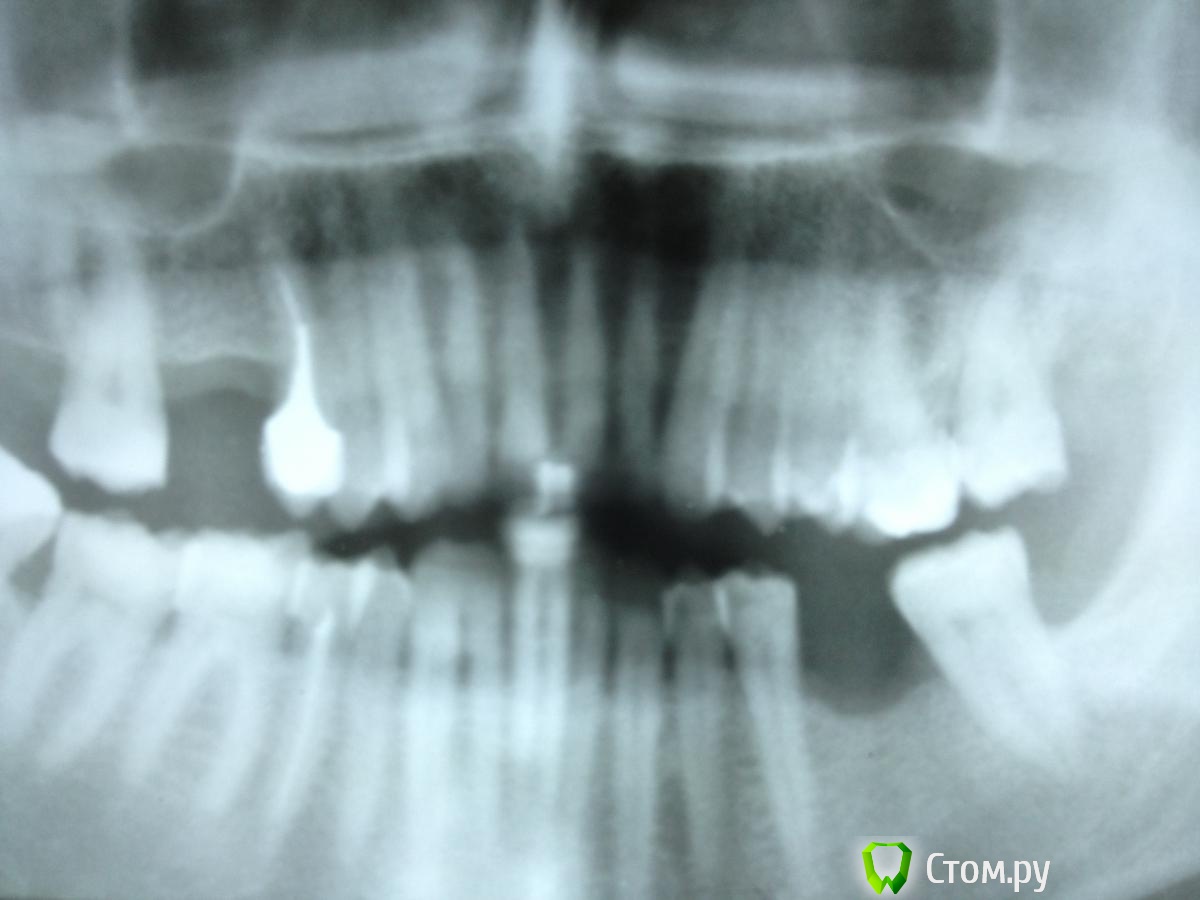

Solnyshko Опубликовано 8 марта, 2014 Поделиться Опубликовано 8 марта, 2014 26 зуб . Пациента беспокоит дискомфорт и отечность слизистой в этой области. Перкуссия безболезненная . Между 26 и 27 зондируется глубокий костный карман. Прошу совета - зуб подлежит удалению? Что вы видите на снимке резорбцию корня или это костный карман? Ссылка на комментарий

Л Ю С Я Опубликовано 8 марта, 2014 Поделиться Опубликовано 8 марта, 2014 Как насчет хорошего контакта между 2.7 и 2.6? Антагонист когда удален? Явно реставрация от 2.6 висит. Проба на витальность ? Ссылка на комментарий

Seryogin Опубликовано 11 марта, 2014 Поделиться Опубликовано 11 марта, 2014 По снимку я бы сказал, что это кариес корня 26. тоже первая мысль при виде снимка. но если приглядеться, то там убыль костной ткани. поэтому участок корня выше уровня кости кажется менее контрастным.) Ссылка на комментарий

Solnyshko Опубликовано 11 марта, 2014 Автор Поделиться Опубликовано 11 марта, 2014 тоже первая мысль при виде снимка. но если приглядеться, то там убыль костной ткани. поэтому участок корня выше уровня кости кажется менее контрастным.) Склоняюсь тоже к этому ,очень сложный выбор у меня.; если откидывать лоскут, то мало толку просто почистить, нужно эмдогейм оставлять, сам шприц стоит 8.5 (на 1 зуб все уйдет) плюс операция 6.5 т. А депульпировать?Нависающие края -это уже мелочи,убрать не сложно. Ссылка на комментарий